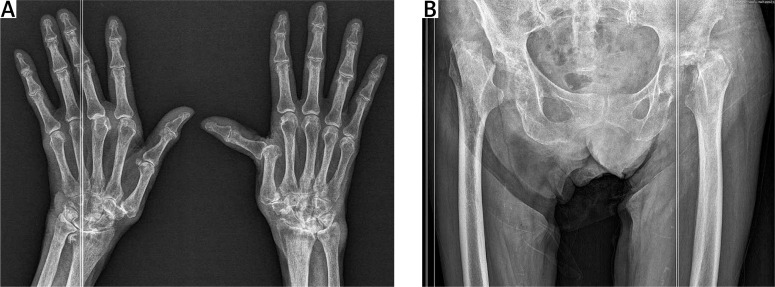

快速破坏性髋关节病(RDC)是一种罕见的髋关节炎,其特点是髋关节迅速恶化。虽然其病因尚不清楚,但已提出了几种病理生理机制。为了全面分析这一鲜为人知的疾病,我们进行了一次文献检索,重点是双侧 RDC 与类风湿性关节炎(RA)的关联。该研究提出了一个问题:长期患有类风湿性关节炎、双侧 RDC 的患者在活动能力急剧下降和髋部剧烈疼痛之前出现发热,放射学评估证实双侧髋部受到破坏。快速破坏性髋关节病,尤其是与 RA 相关时,给诊断和治疗带来了挑战。我们的综述与临床表现相印证,强调了对髋关节受累的 RA 患者保持警惕的必要性,并呼吁开展进一步研究,以了解 RDC 的机制并加强临床护理。

Rapidly destructive coxopathy (RDC) is a rare type of coxarthritis marked by swift deterioration of the hip joint. Although its cause remains unclear, several pathophysiological mechanisms are proposed. To comprehensively analyze this poorly understood condition, a literature search was conducted focusing on associations of bilateral RDC and rheumatoid arthritis (RA). The problem of long-standing RA, bilateral RDC with a febrile episode that preceded a rapid decline in mobility and severe hip pain, with radiological assessment confirmed bilateral hip destruction, was presented. Rapidly destructive coxopathy, especially when linked to RA, poses diagnostic and therapeutic challenges. Our review confirmed by the clinical picture emphasizes the need for vigilance in RA patients with hip involvement and calls for further research to understand RDC's mechanisms and enhance clinical care.